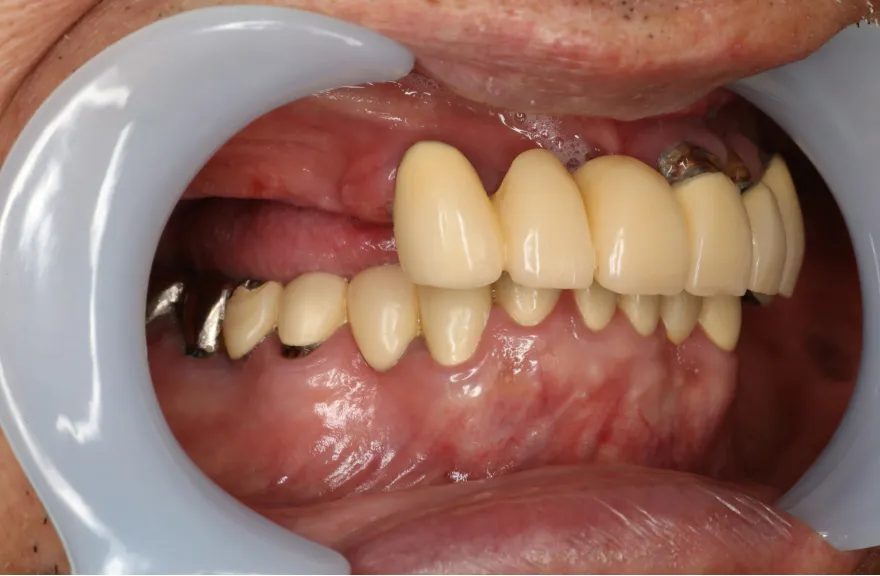

写真の通りに治療を終了いたしました。

上顎は総義歯の形態に、下顎は十分な寿命を持った歯は残して、長期的な保存が難しい歯はインプラント治療を施しました。上顎を総義歯形態にすることにより、何かが起こっても義歯の修理を行えば対応が可能です。即日の修理・完了も難しくないでしょう。

下顎は十分な寿命を持った歯しか残していないので、今後の人生でよっぽどのことがない限りトラブルが起きないと考えます。インプラント治療を施してある部分も、同様にトラブルが起きにくいと考えています。歯周病になった、とか歯が欠けた、というインプラント治療の悪い面が聞こえてくるようになりましたが、噛み合う上の歯を総義歯とすることで、過大な力がかかることなく、トラブルが起きにくい結果を得ることができました。

上顎は総義歯ですが、『今まで食べられなかったものがなんでも噛めるようになった』と、患者さんよりお言葉を頂戴しております。